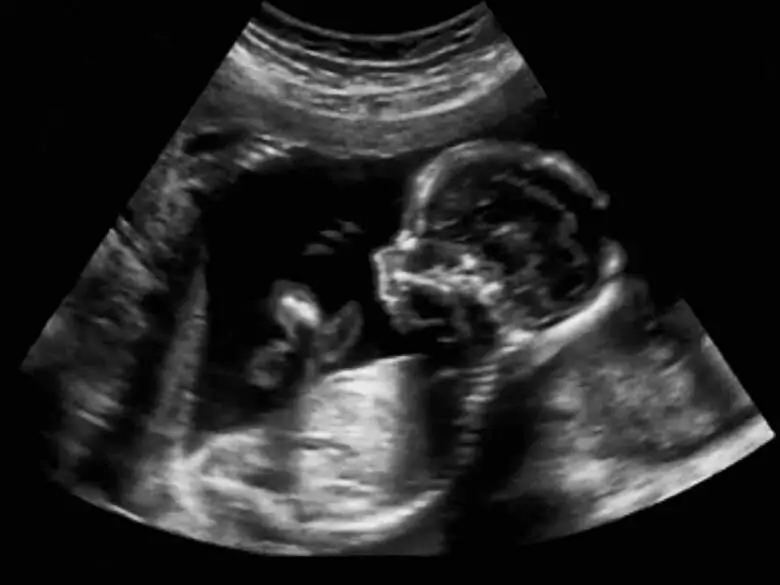

Badania prenatalne od dawna odgrywały istotną rolą w ginekologii i położnictwie, współcześnie jednak ich wartość stale się zwiększa z powodu tego, że coraz więcej kobiet późno zachodzi w ciążę. Wśród badań prenatalnych wyróżnia się zarówno inwazyjne, jak i całkowicie nieinwazyjne badania – jakie dokładnie badania wykonywane są w diagnostyce prenatalnej i kiedy korzysta się z poszczególnych z nich?